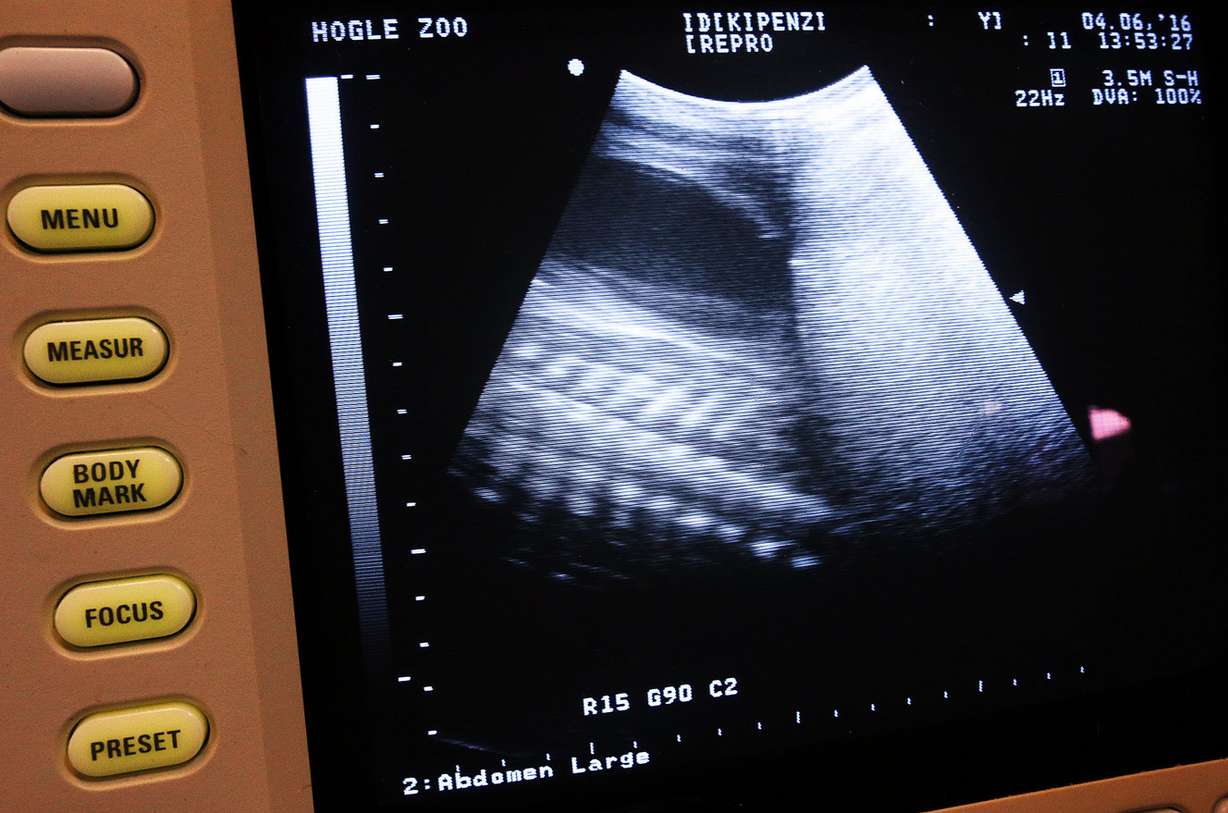

"Kipenzi is one of our best giraffes, we do a lot of work with her. She tolerates an awful lot, and in her mind, if she's being fed she probably doesn't care what I'm doing when I'm ultrasounding her," said Dr. Nancy Carpenter, senior veterinarian and associate director of animal health at Utah's Hogle Zoo. She said Kipenzi isn't restrained during the noninvasive procedure and the ultrasound is only intended to monitor the baby inside, not because of any concern for its well-being.

The "full-figured" giraffe, Carpenter said, is pregnant for the third time and has undergone at least three ultrasounds in the first eight months of her nearly 15-month gestational period. The baby is expected to drop some time in December and could weigh close to 150 pounds and stand around 6 feet tall.

The gender of the fetus is unknown, as only a more invasive and unnecessary type of ultrasound would be required to detect such detail, Carpenter said. It won't matter, as either gender might end up being separated from the mother sometime after birth.

Positive reinforcement is used to "desensitize" the animals, she said, and prepare them for any potential interventions. The situation was favorable enough with Kipenzi that an ultrasound could be done. The procedure isn't common among animals, and especially giraffes due to their size.